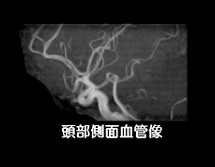

MRIは磁気共鳴画像とも呼ばれ、強い磁石と電波を使って、身体のあらゆる部位を撮影できる装置です。放射線を使用しないので被ばくの心配はなく、ラジオ波と同じ電波を利用して撮影しているため人体に優しい検査法です。 X線の画像と比べて筋肉・脊髄・内臓などが、明瞭かつ詳細に描出されます。MRIが有用なのは、脳梗塞・脳腫瘍などの脳疾患、動脈瘤などの血管障害、がん・子宮筋腫・椎間板ヘルニア・靭帯断裂など動きの小さい柔らかい組織での病変描出に適しています。 MRIの特性を利用して、造影剤を使わずに脳血管像(MRA) 胆管・膵管像(MRCP)の描出も可能です 。

| 脳血管像(MRA) | 胆管・膵管の検査(MRCP) | |